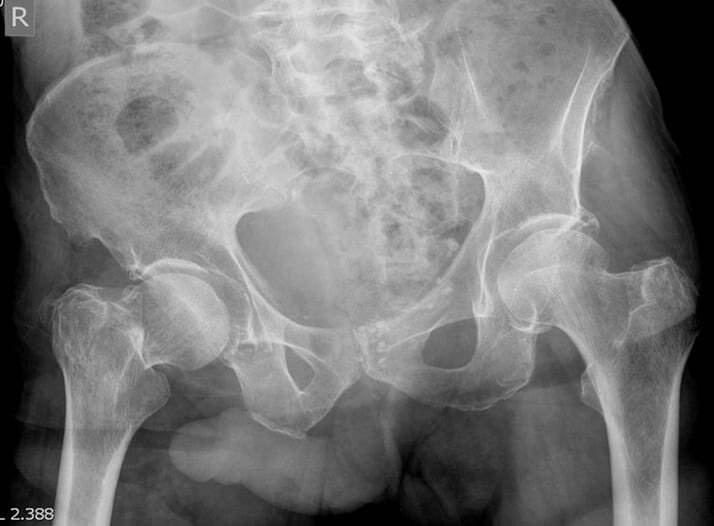

На снимке ниже мы видим перелом шейки бедра справа и положительный симптом Джона Томаса.

перелом шейки бедра справа и положительный симптом Джона Томаса